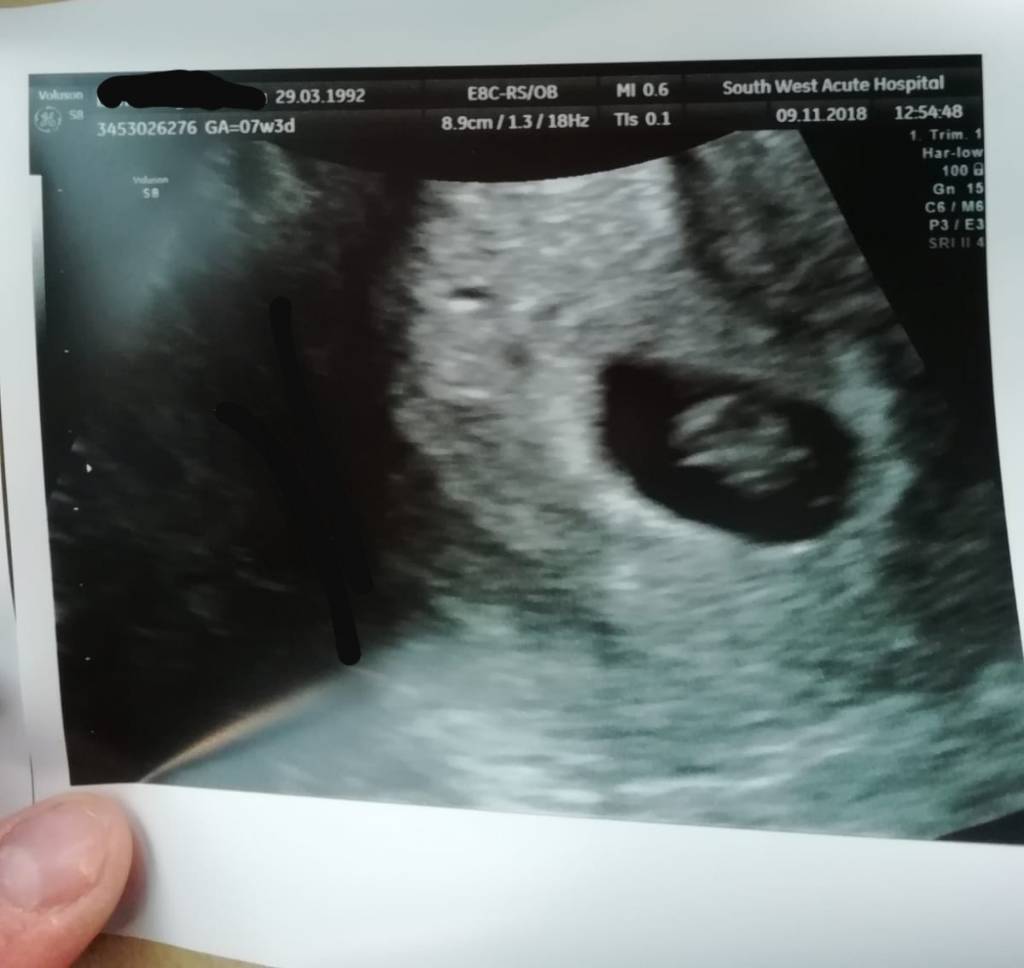

Jest fasolka , serduszko bije i wszystko ok. Termin z USG 3.07![]()